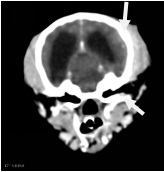

| 右侧眼眶壁内前侧骨折 |

| 右侧顶骨及颞骨骨折 |

| 大脑右侧顶部脑挫裂伤 |

| 先天性脑囟门未闭合;右侧耳道少许积液 |

1、右侧眼眶壁骨折

2、右侧顶骨及颞骨骨折伴周围软组织稍肿胀

3、大脑右侧顶部脑挫裂伤

4、先天性脑囟门未闭合

5、右侧耳道少许积液

余未见明显异常,请结合临床。